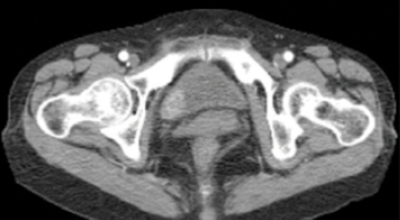

방광은 몸으로 섭취된 물이 신장을 통해 소변으로 배출되기 전에 저장되는 곳을 말합니다. 소변은 온몸을 돌고 온 혈액이 신장에서 걸러져 나온 부산물로서 성인의 1.5~2L가량 만들어진다고 합니다. 이렇게 생성된 소변은 요관을 통해 방광으로 이동하게 되고 소변이 어느 정도 차게 되면 대뇌로부터 배뇨 신호를 받아 방광의 출구가 열리면서 소변으로 배출하는 배뇨 활동을 합니다. 방광에 문제가 생기면 배뇨 활동에 영향을 주어 소변이 새거나 안 나오는 증상부터 혈뇨 등에 문제가 발생합니다.

방광암은 여성보다 남성에게 발생할 확률이 상대적으로 높은 대표적 3대 비뇨기암으로 유명하고, 비뇨기계 암 중 발병률이 높아 남성암 중에선 7위라는 타이틀을 차지하고 있어요. 2017년 기준으로 보면 국내에서는 약 4400명이 방광암으로 진단받았으며 그중에서도 약 80프로가 고령 환자였다고 합니다.

방광암 초기증상

3. 방광암 초기증상 - 혈뇨

4. 방광암 초기증상 - 배뇨장애 또는 배뇨통